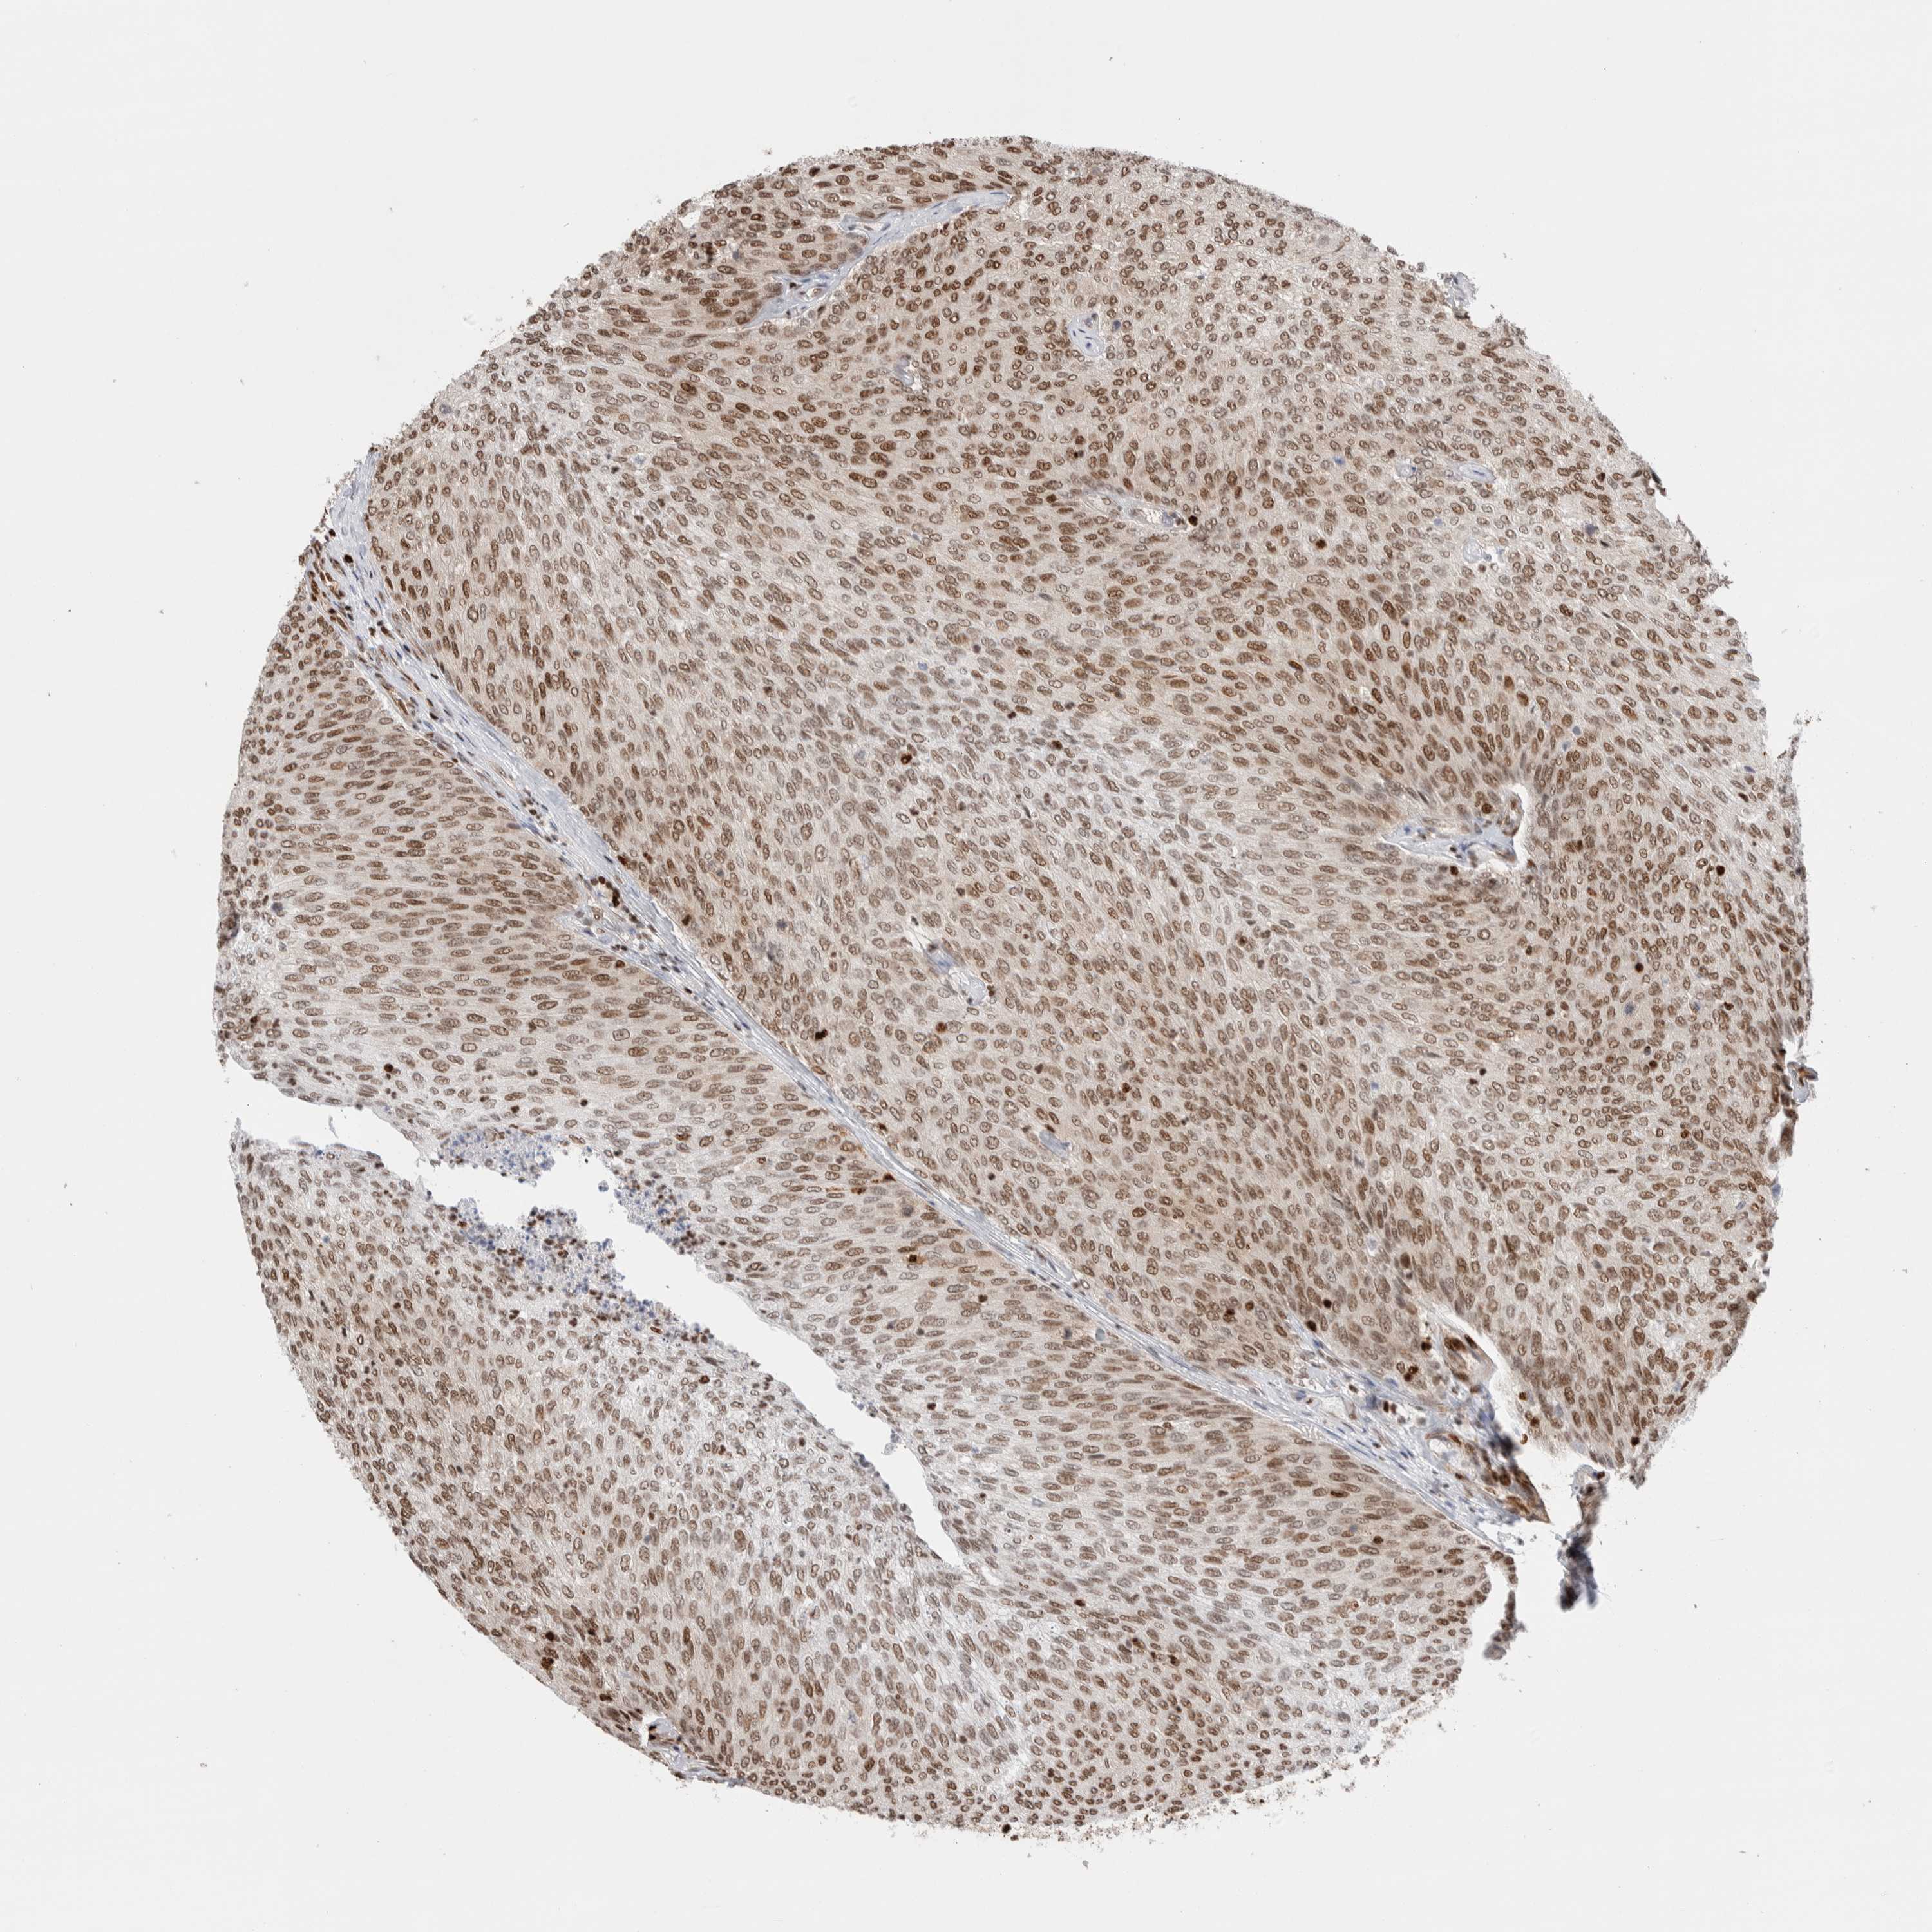

UROTHELIAL CANCER - Protein expressioni

A mouse-over function shows sample information and annotation data. Click on an image to view it in a full screen mode. Samples can be filtered based on level of antibody staining by selecting one or several of the following categories: high, medium, low and not detected. The assay and annotation is described here.

Note that samples used for immunohistochemistry by the Human Protein Atlas do not correspond to samples in the TCGA dataset.

Antibody stainingi

Antibody staining in the annotated cell types in the current human tissue is reported as not detected, low, medium, or high, based on conventional immunohistochemistry profiling in selected tissues. This score is based on the combination of the staining intensity and fraction of stained cells.

Each image is clickable and will lead to virtual microscopy that enables deeper exploration of all samples and also displays staining intensity scores, fraction scores and subcellular localization as well as patient and tissue information for each sample.

Antibody HPA022961

Antibody HPA024457

Staining

High

Medium

Low

Not detected

Intensity

Strong

Moderate

Weak

Negative

Quantity

>75%

75%-25%

<25%

None

Location

Nuclear

Cytoplasmic/membranous

Cytoplasmic/membranous,nuclear

Urothelial carcinoma, Low grade

Urothelial carcinoma, High grade